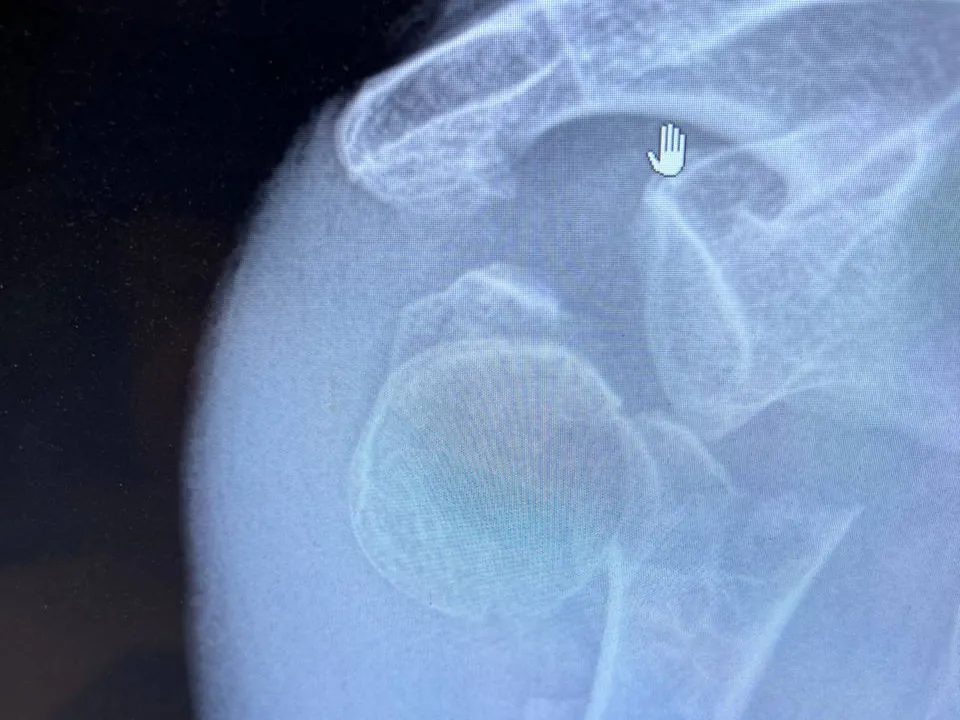

Врачи Подольской больницы провели уникальную операцию пожилой пациенткеВ Подольскую областную клиническую больницу обратилась 77-летняя пациентка с переломом шейки плечевой кости.

Данная травма является одной из наиболее частых у пожилых людей, и восстановиться после такого повреждения бывает очень непросто. Многооскольчатые переломы лишают врачей возможности надежно зафиксировать отломки кости между собой и воссоздать анатомию сустава. Эндопротезирование для пенсионеров тоже не выход, так как при остеопорозе процесс может осложниться нестабильностью компонентов.

Поэтому для лечения пациентки травматологи Подольской больницы решили провести остеосинтез шейки плечевой кости пластиной с использованием костного аутотрансплантата размером 6,5 см. Его пересади с малоберцовой кости. Такая операция стала первой в московском регионе.

Место забора костного трансплантата пациентку не беспокоит. Уже на следующий день после операции она самостоятельно передвигалась по отделению.